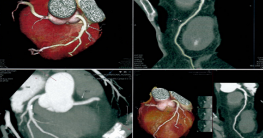

Chụp CT mạch vành là kỹ thuật sử dụng máy chụp cắt lớp vi tính đa lát cắt (MSCT-Multí-Slice Computerized Tomography scan) để hiển thị hình ảnh hệ thống động mạch bên trong tim của người bệnh. Thông qua kỹ thuật chụp này, bác sĩ có thể quan sát, kiểm tra được các mảng bám chứa canxi trên thành động mạch. Từ đó có thể phát hiện bệnh động mạch vành kể cả khi người bệnh chưa có dấu hiệu hay triệu chứng bệnh.

Ngoài ra, kỹ thuật chụp CT hay chụp MSCT mạch vành còn giúp hỗ trợ chẩn đoán các bệnh lý, cấu trúc, khảo sát chức năng tim, giúp bác sĩ lựa chọn biện pháp điều trị hiệu quả nhất.

Thông qua kỹ thuật chụp MSCT mạch vành, bác sĩ có thể đánh giá lòng mạch vành và thành mạch vành. Như vậy, dễ dàng khảo sát được hình thái và cấu trúc các mảng xơ vữa, đưa ra đánh giá về tình trạng hẹp mạch vành của người bệnh.

Chụp động mạch vành có cản quang là kỹ thuật tiêm thuốc cản quang vào trong lòng động mạch trước khi chụp CT. Như vậy, trong quá trình chụp thì hình ảnh của hệ động mạch được hiển thị rõ ràng hơn, giúp bác sĩ có thể đánh giá chính xác được những tổn thương của hệ thống động mạch vành.

Kỹ thuật chụp CT mạch vành có tiêm thuốc cản quang có hiệu quả lên đến hơn 97%, đánh giá được nhiều bệnh như hẹp mạch vành, tắc động mạch vành, dị dạng xuất phát hay đường đi của động mạch vành, dò mạch vành vào buồng tim… cũng như những bất thường cấu trúc, chức năng tim. Nhờ đó, bác sĩ có thể đưa ra chẩn đoán bệnh chính xác nhờ đó có cách điều trị tối ưu nhất.